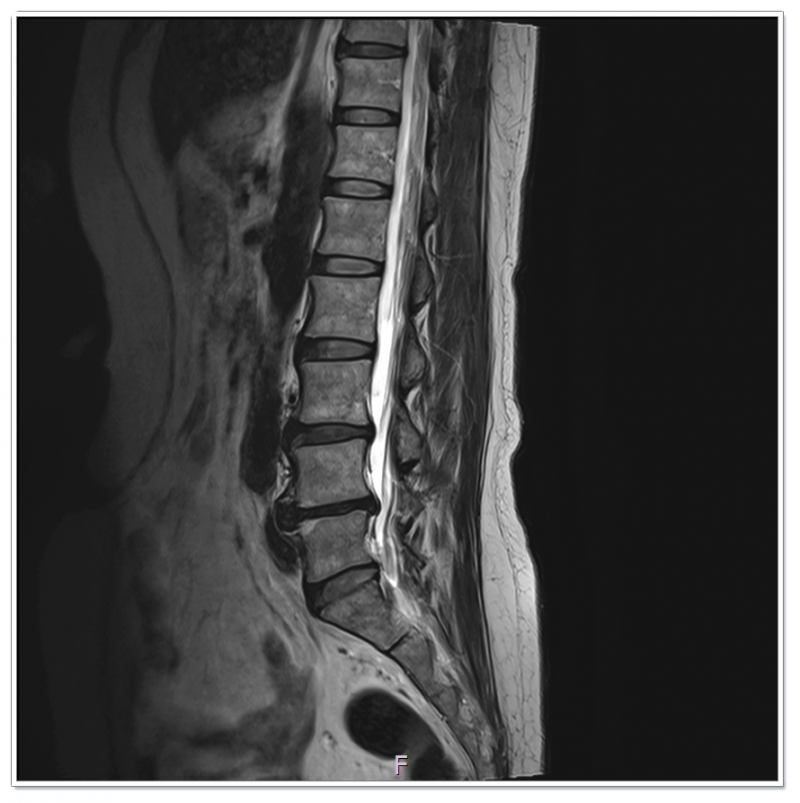

우리 몸에는 24개의 척추뼈가 있고, 이 구조가 중력을 버티며 하루 종일 신체를 지탱하고 있습니다.

그 과정에서 하부에 위치한 요추 3·4·5번에 압력이 집중되게 됩니다.

디스크 질환은 이러한 압력이 오랜 시간 반복되며 누적된 결과에 가깝습니다.

“요추 3·4·5번 디스크 문제는

허리 하나의 문제가 아닙니다.”

골반과 자세, 그리고 생활 습관이 쌓여 나타난 결과입니다.